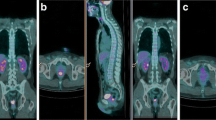

Results from univariate linear regression analysis comparing metabolic parameters to TRG groups are shown in Fig. 1. Among all the metabolic parameters considered in our study, a direct significant correlation with TRG groups was found for SUV2 (P = 0.048) and mostly for SUV3 (P = 0.009), but only the latter parameter was significantly correlated to TRG in a multivariate analysis (P = 0.002).

An example of PET/CT studies in a patient with metabolic response is reported. There is a significant decrease of SUV values from 11.2 in PET/CT1 study (first row) to 7.0 and 2.2 in PET/CT2 and PET/CT3, respectively (second and third rows). deltaSUV1 and deltaSUV2 were 37.5% and 80.4%, respectively. TRG on rectal specimen was 2.

An example of PET/CT studies in a metabolic non-responder patient is reported. The SUV value of the rectal lesion (white arrows) was 22.8 in PET/CT1 study (first row) and decreased to 13.9 and 5.5 in PET/CT2 and PET/CT3, respectively (second and third rows). deltaSUV1 and deltaSUV2 were 39.0% and 75.9%, respectively. TRG on rectal specimen was 4.